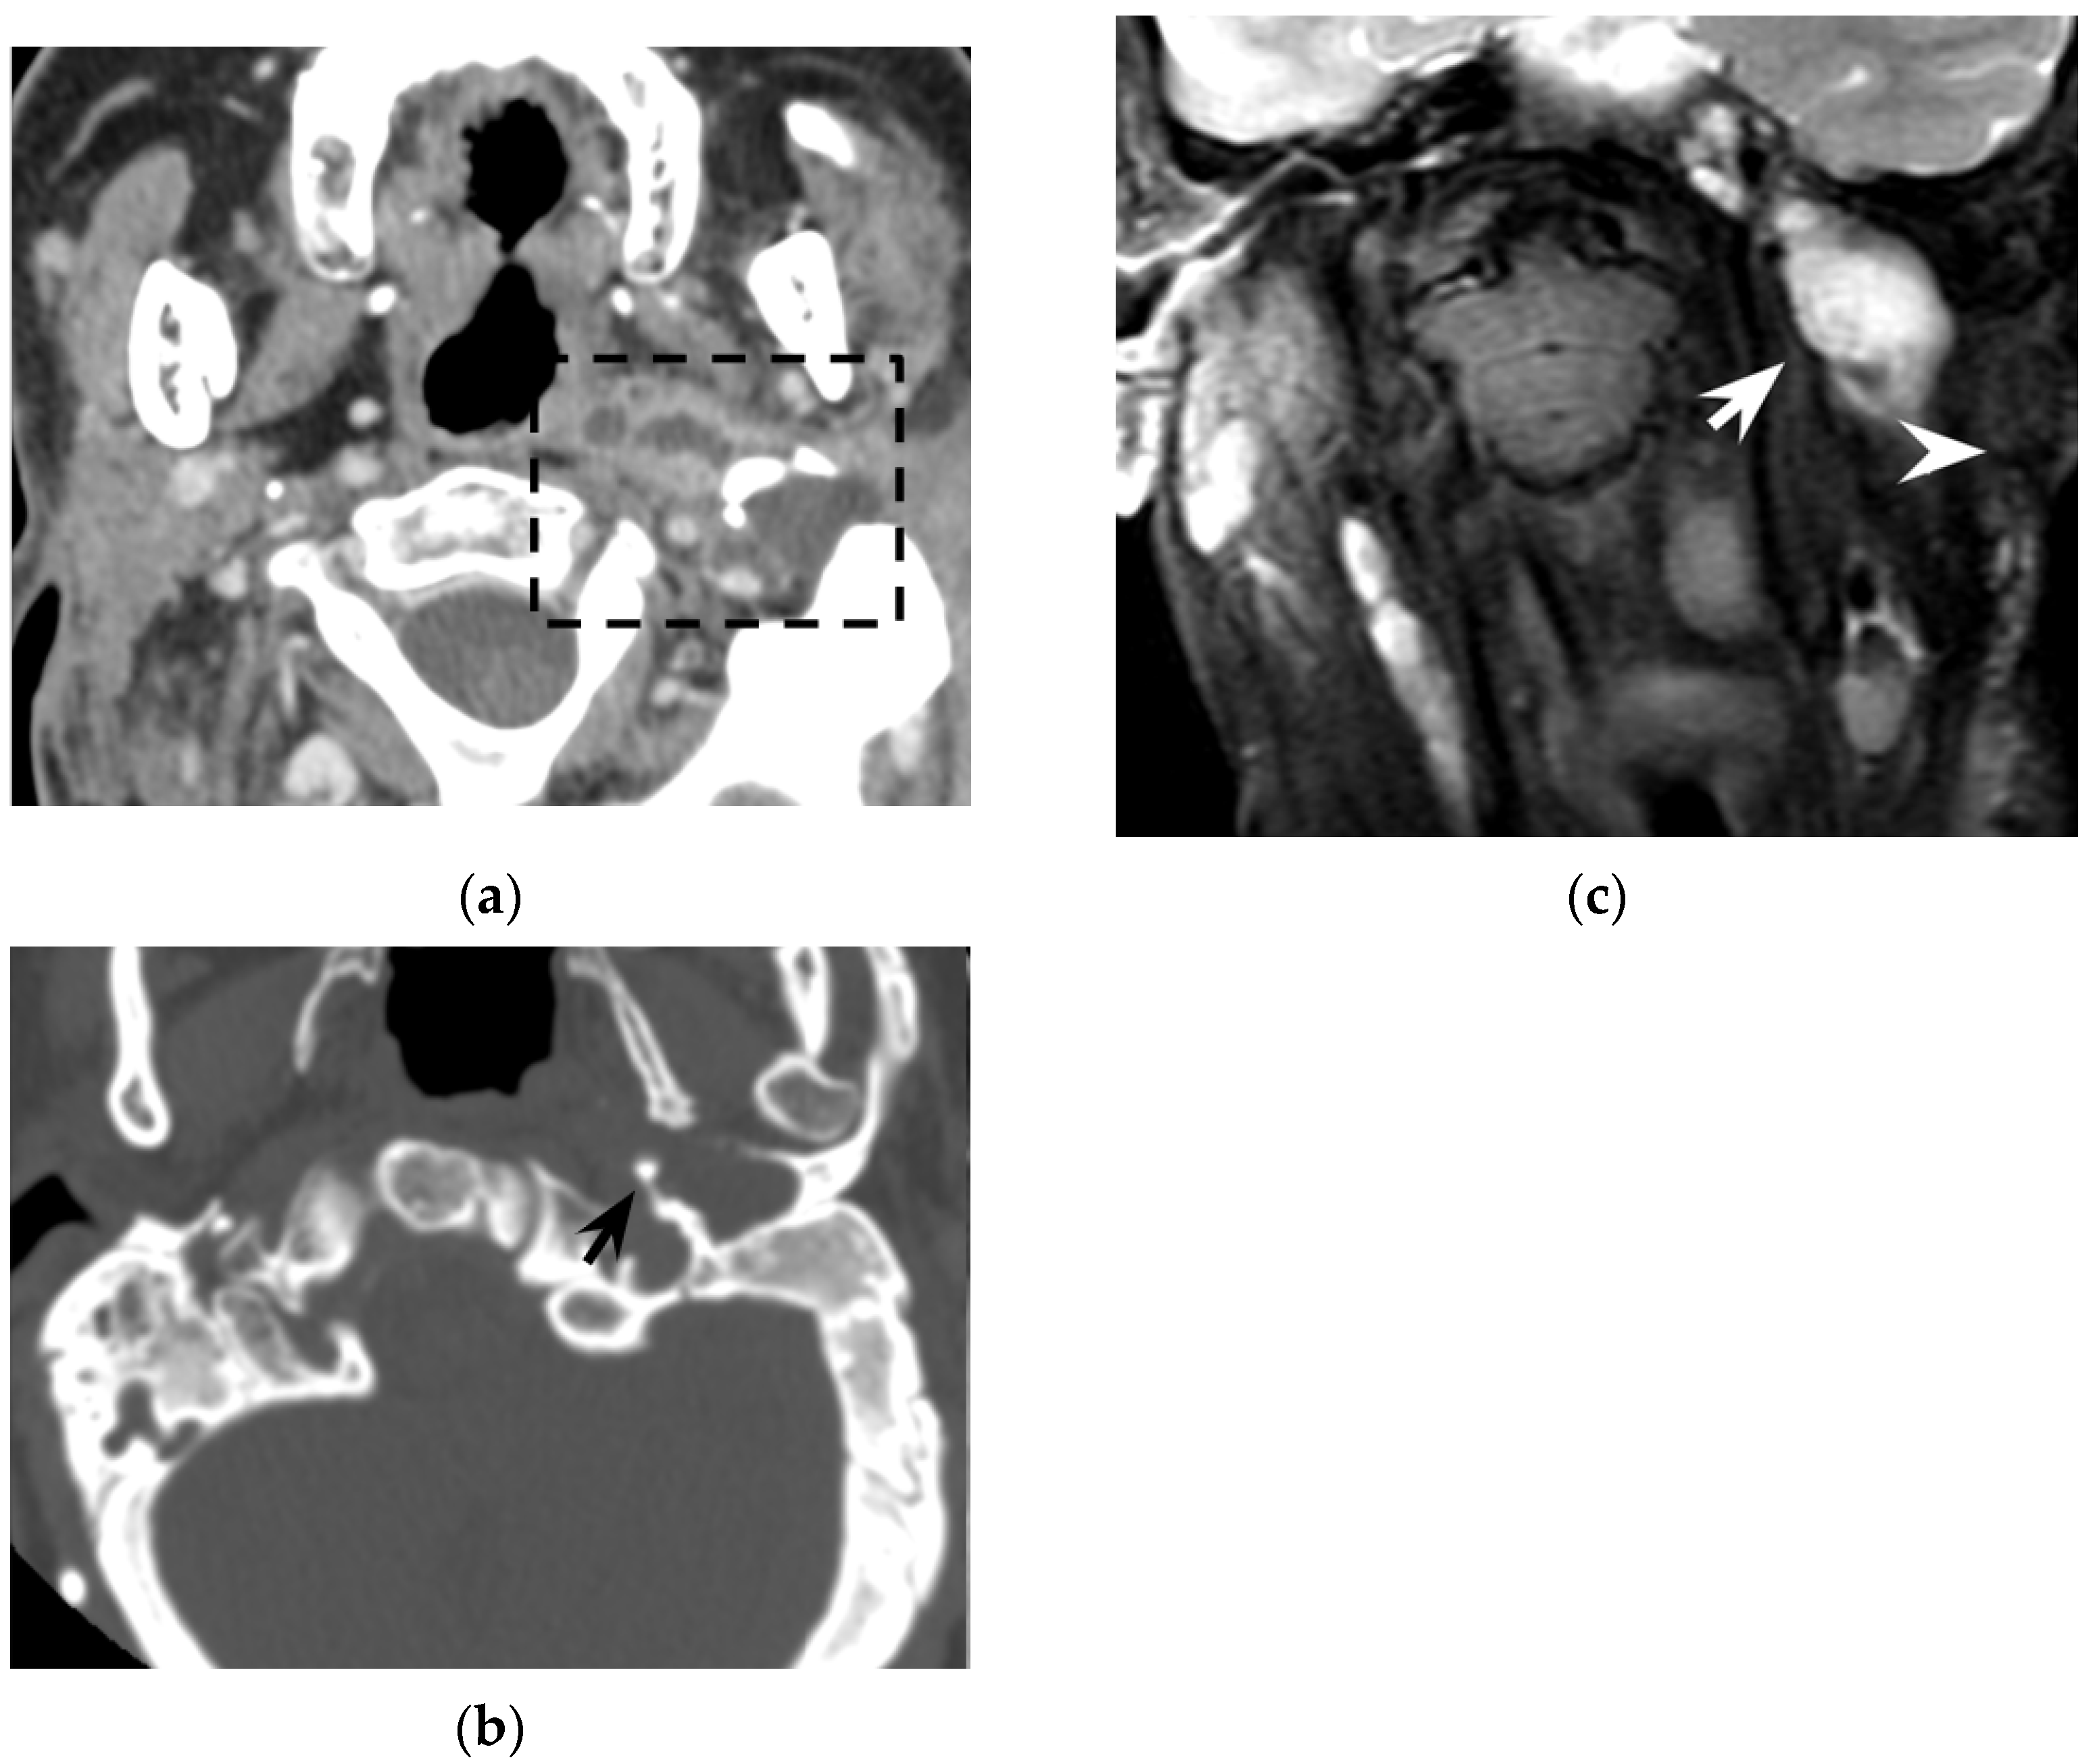

In the literature, cholesteatoma ipsilateral to Bezold’s abscess was reported in around 40% of patients. Cholesteatoma likely favors repeated mastoid bacterial superinfections and facilitates, by bone erosion, the spread of suppurative process into the neck (see Section 4.2). In several patients, cholesteatoma was diagnosed at surgery (11/97) and in a few cases it was partially an unexpected finding. However, MRI might easily recognize cholesteatoma preoperatively as these cysts appear as strikingly hyperintense DWI ovoid masses [42]. Differently from purulent collections, apparent diffusion coefficient (ADC) values might be slightly increased in cholesteatomas, suggesting a T2 shine-through effect more than a true water diffusion restriction [55]. From a technical point of view, whereas investigating the mastoid and the upper neck, non-echo-planar (non-EPI) DWI sequences should be preferred to minimize mastoid air/bone susceptibility artifacts that could mask the cholesteatoma [56]. DWI represents a very powerful tool also in postoperative and follow-up examinations, allowing for the detection of small cholesteatomatous residuals or recurrences (Figure 6), especially those with a diameter larger than 2–4 mm [57].

Figure 6. Thirty-seven-year-old man with chronic otitis media and history of ear surgery. MRI T1w (a) and contrast-enhanced T1w (b) sequences showing hypo-isointense material in the left mastoid (black arrows) spreading in the neck, in the posterior cervical space (white arrowheads). Note the mastoid mucosal enhancement, suggestive for mastoiditis, and the peripheral enhancement of the neck component (b). The material in the mastoid is hyperintense in diffusion-weighted imaging (c) and shows inhomogeneous apparent diffusion coefficient values (d), consistent with purulent collection and cholesteatoma. Bezold’s abscess and left mastoid cholesteatoma were confirmed at surgery.